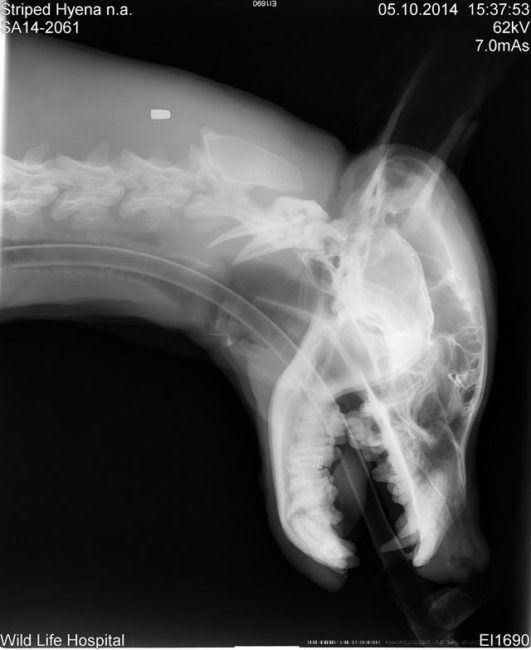

Οι κτηνίατροι προσπάθησαν να σταθεροποιήσουν την κατάσταση της ύαινας καθώς έκαναν διάφορες εξετάσεις για να καταλάβουν το πλήρες εύρος των τραυμάτων της. Ενώ μπορούσαν εύκολα να αναγνωρίσουν τους εξωτερικούς τραυματισμούς, δεν είχαν ιδέα τι συνέβαινε μέσα στο καημένο πλάσμα.

Οι μελανιές όμως δεν ήταν τα μόνα της τραύματα. Είχε πολλά σπασμένα δόντια επίσης. Κάποια ήταν κομμένα μέχρι τη ρίζα και αυτό πρέπει να της προκαλούσε φρικτό πόνο.

Τελικά, βγήκαν και οι υπόλοιπες εξετάσεις και έδειξαν πως είχε πολλά σπασμένα κόκαλα σε όλο του το σώμα.

Ο χειρότερος τραυματισμός του ήταν πως είχε σπασμένο μπροστινό πόδι και πατούσα. Φάνηκε σαν να είχε πιαστεί σε κάποια παγίδα και αυτό θα μπορούσε να εξηγήσει τον τρόπο που βρέθηκε σε αιχμαλωσία.